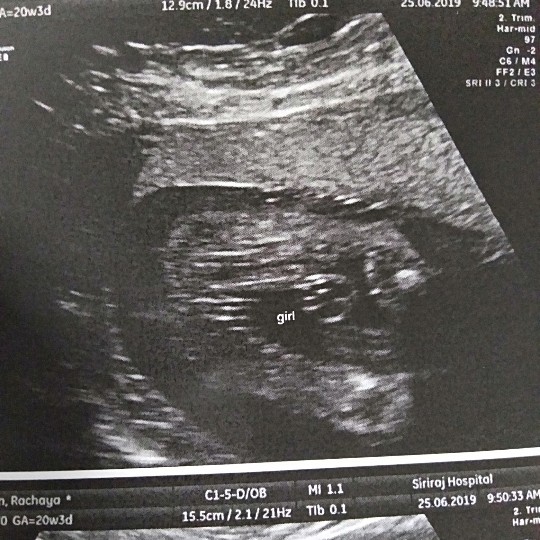

เเชร์กันน่อยค่ะ เเม่ๆบ้านไหน ได้ลูกสาวบ้างค่ะ เเล้วคลอดเดือนไหนกันบ้างค่ะ บ้านนี้ได้ลูกสาว ตื่นเต้นมากๆๆๆค่ะ

ลูกสาวค่ะ กำหนดคลอด 27สิงหา👶🏻👶🏻